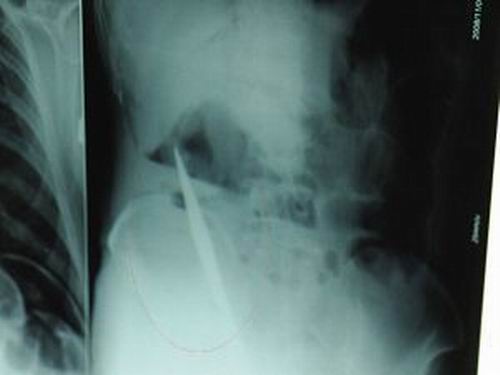

X光片上,尖刀清晰可見。

從男子體內取出的尖刀足足有19厘米長。

昨天(11月6日)上午,記者在徐州礦務集團總醫(yī)院重癥監(jiān)護室見到了這名男子,目前他雖然已經恢復了意識,但還不能開口說話,需要呼吸機輔助呼吸。據醫(yī)生介紹,4日中午12時左右,這名男子因服毒輕生被緊急送到醫(yī)院進行搶救,之前,這名男子已經在當地鄉(xiāng)鎮(zhèn)醫(yī)院進行了近20小時的治療,但效果不佳!安∪吮晦D院到礦總院時已神志不清,血壓極低,處于休克狀態(tài)。”救護人員給男子洗胃、初步處理以后,發(fā)現(xiàn)男子呼吸急促,于是趕緊給他拍片檢查。結果讓所有的醫(yī)生大吃一驚,竟有一把尖狀異物橫在該男子腹腔內!當天下午5時30分,輕生男子被推上了手術臺。經過40多分鐘的手術,該男子腹腔被打開,手術醫(yī)生發(fā)現(xiàn),男子體內的金屬狀異物竟然是一把長19厘米的尖刀!

醫(yī)生告訴記者,手術后,醫(yī)生在病人身上并未發(fā)現(xiàn)刀痕,最后,經過檢查發(fā)現(xiàn),在該男子直腸處找到穿孔。醫(yī)生從醫(yī)學角度分析后認為,這把尖刀應該是從肛門插入直腸的。